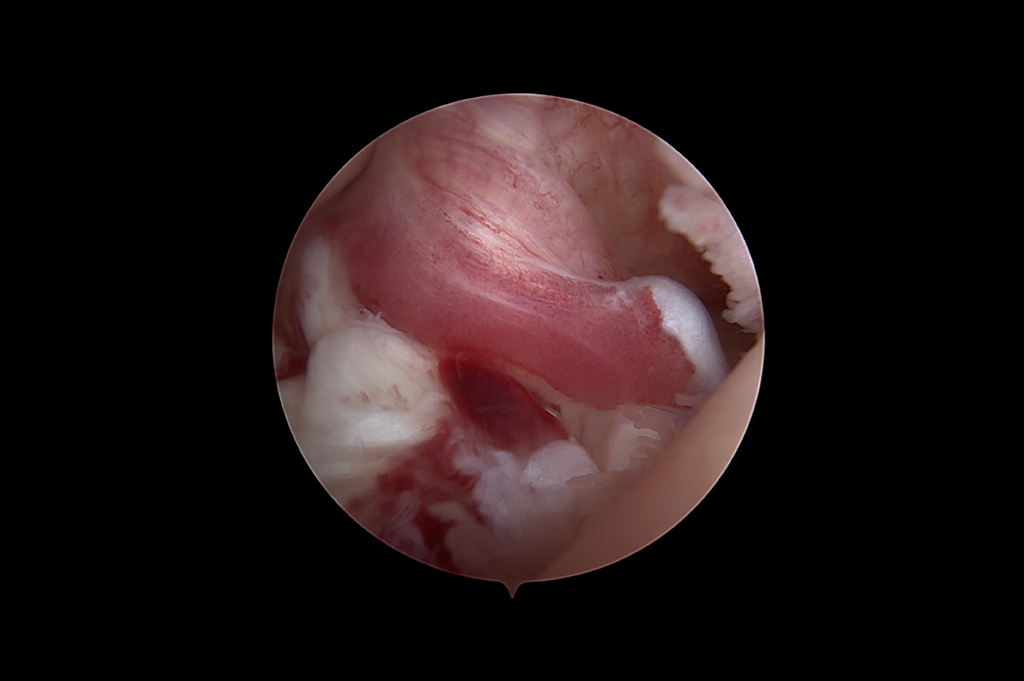

Arthroscopy - ACL Reconstruction, Maniscus Injury